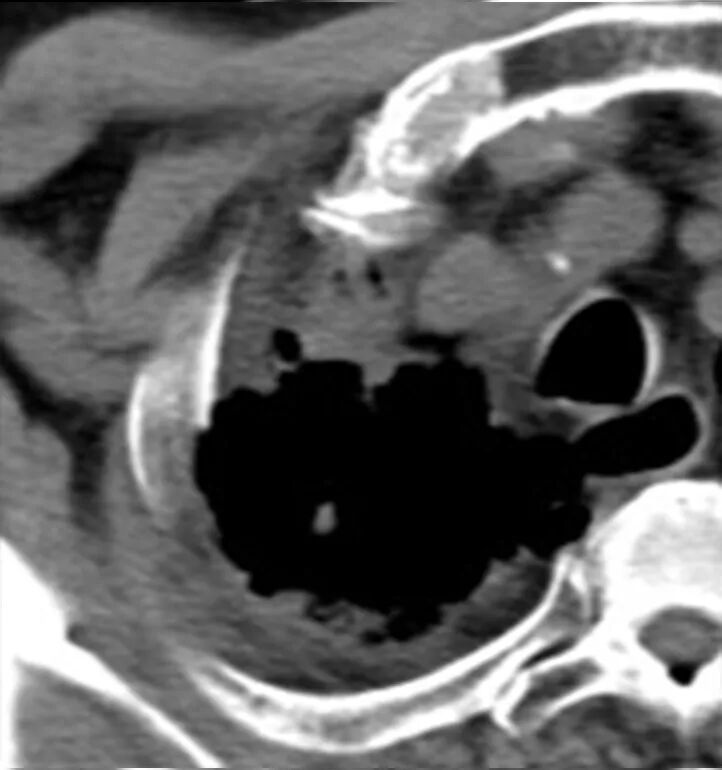

去年5月初,王大伯因冠心病住进了康华医院,查胸部CT时意外发现右肺上叶有一个肿块,直径约2cm,医生建议他做进一步检查,但大伯和家属都没有重视,“八成没问题的,不用再检查了”。待王大伯冠心病症状得到控制后,他便出院了。

同年11月,王大伯又因为头晕住院了,再次查胸部CT时发现右肺上叶肿块增大到3.5cm了,“考虑右肺上叶肺癌”——报告如此显示。仅半年时间竟长得这么快,大家都慌了,赶紧找到肿瘤科主任王剑飞咨询对策。

经过王剑飞和肿瘤中心MDT团队的认真讨论,确诊王大伯为右肺恶性肿瘤。“那要手术么?”家属着急地询问着。“大伯80多岁了,心肺功能也不好,手术治疗不耐受的,还是考虑局部治疗,也就是放射治疗”,王剑飞耐心解释着。 经过考虑,大伯和家属都接受了放射治疗的建议。放疗中心副主任刘文君、主治医师阮龙飞为王大伯详细制定了右肺上叶肿块根治性放疗的治疗方案。很快,王大伯便正式开始了治疗。 一年过去了,王大伯早已结束了治疗,而他的定期复查结果令人欣喜——右肺上叶肿块持续缩小,现在已经几乎消失了! “还好听医生话还算及时!”每次看到复查报告,王大伯都十分高兴,一再感谢肿瘤科团队的帮助与悉心照料。 王剑飞提醒市民:发现肿瘤并不是最可怕的,可怕的是不重视或不配合治疗,这是医生最无能为力的局面。 治疗前 治疗结束 治疗结束后2月 治疗结束后10月